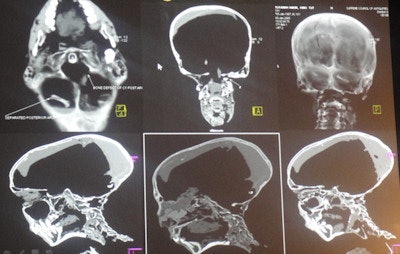

"These people really knew their anatomy," he told ICR delegates of the ancient Egyptians who performed the mummification. "The first step in mummification was to introduce an iron rod in one of the nostrils, breaking the cribriform plate of the ethmoid bone, which is the thinnest part of the skull base, so they could extract all the brain out of the nostrils, and then they poured in the embalming material."

Because the organs were full of water and would putrefy, the ancient Egyptians removed them and stored them in canopic jars put next to the mummies' bodies. This was done to ensure that the mummies would enter the afterlife, Selim explained. They removed all organs except the heart, because they were convinced the soul returned via the heart.

Complete dehydration was essential to achieve successful mummification, he added. The ancient Egyptians did that by packing the body with linen bandages soaked in natural salt, which imbibed water from the tissues, and they also added ointments to make sure the body smelt pleasant. Then they left the body to dry out for between 40 days and 70 days, which is why some Arab cultures still celebrate the 40th day after a death has occurred.